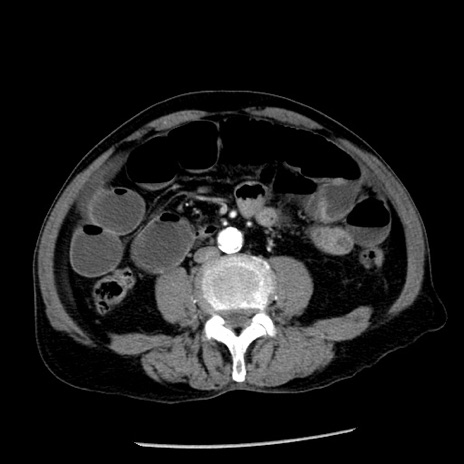

症例26(横断像)

【症例】80歳代男性

【主訴】嘔吐

【現病歴】昨晩2回嘔吐あり、今朝になっても嘔吐あり。来院。

【既往歴】胃潰瘍

【身体所見】意識清明、BT 37.6℃、BP 166/95mmHg、HR 100bpm、SpO2 97%、腹部:平坦・軟、腸蠕動音聴取良好、圧痛なし。

【データ】WBC 21900、CRP 1.46